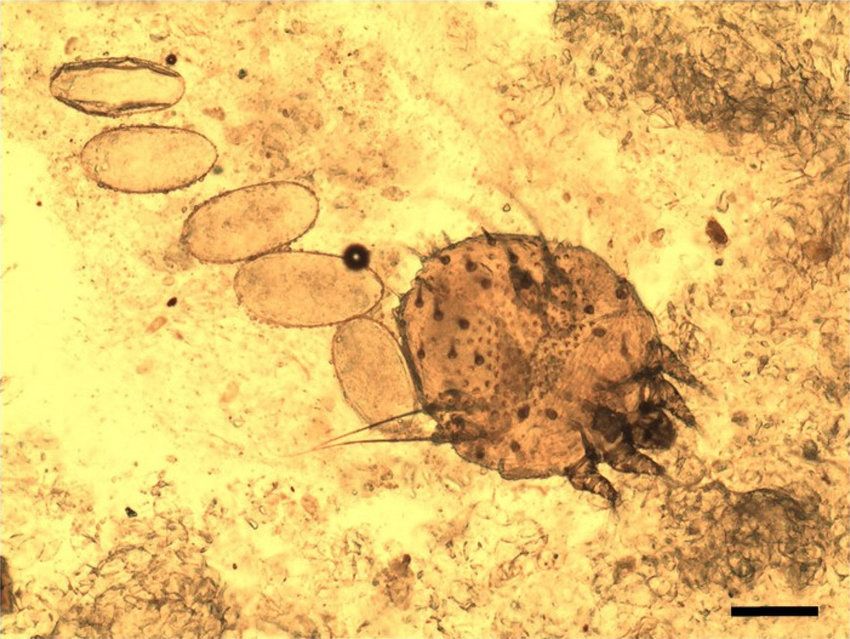

Scabies is caused by infection with the female mite Sarcoptes scabiei var. hominis,